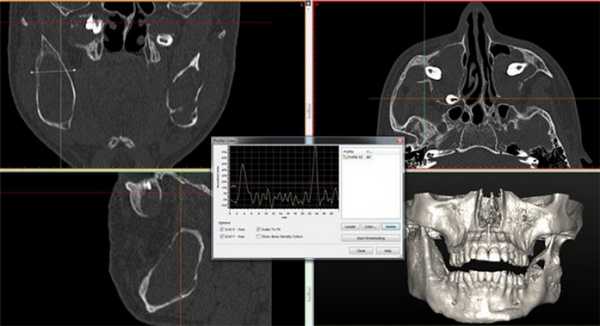

Сегодня технология конусно-лучевой компьютерной томографии (КЛКТ) позволила при минимальной дозе облучения, получить истинно многоплоскостные и 3D-изображения структур челюстно-лицевой области и дала толчок к большому объему исследований с целью диагностики и оценки патологии в области головы и шеи.

Рис. 1. КТ свидетельствует об остеосаркоме, опухолевый инфильтрат происходит из передней стенки верхней челюсти слева, с вовлечением альвеолярной кости (остеолиз).

Рис. 2. КТ свидетельствует об остеосаркоме, поражена левая половина верхней челюсти, вовлечены крыловидный отросток и нижняя челюсть с инфильтрацией в виде солнечных лучей и выраженной периостальной реакцией. Ассоциированные деформация и отек мягких тканей.

Рис. 3. 3d-реконструкция остеосаркомы с деформацией и отеком мягких тканей.

Рис. 4. КТ свидетельствует о рецидиве кистозной формы амелобластомы.

Поражено тело нижней челюсти больше справа, определяется «вздутие» и неравномерное истончение передней пластины тела челюстной кости, обширный участок деструкции с четкими, полицикличными контурами, неправильной овальной формы, размерами 4,5 х 3,5 х 3,0 см. Кортикальный слой передней поверхности челюсти значительно истончен, местами не определяется, периостальная реакция отсутствует. В патологически измененном участке видны перегородки и известковые включения. Правое ментальное отверстие и дистальный отдел канала правого нижнеальвеолярного нерва не определяется.

Рис. 5. КТ свидетельствует об объемном образовании нижней челюсти, требующем верификации.

Поражена правая ветвь нижней челюсти. Определяется объемное кистозное образование, овальной формы с четкими полицикличными контурами, замещающее весь венечный отросток и распространяющееся на суставной отросток. Объем кости увеличен за счет вздутия. Кортикальный слой значительно истончен, местами не прослеживается. Канал нижнеальвеолярного нерва вплотную прилежит к образованию, верхняя его стенка в проксимальном отделе не прослеживается. В подьязычной области справа виден лимфоузел, размерами 1,7 на 0,9 см.

Рис. 6. Ортопантомограмма пациента с одонтогенными кератокистами.

КТ свидетельствует о наличии множественных одонтогенных кератокист. Определяются множественные овальные, зубосодержащие полости, с четкими ровными справа и полицикличными контурами слева, однородной рентгенпрозрачности. В теле и ветвях нижней челюсти образование распространяется вдоль кости от премоляров справа и моляров слева и до вершин мыщелковых отростков. Костные структуры незначительно увеличены в размерах за счет вздутия, кортикальные пластины истончены. Дивергенция корней зубов № 43, 44. Объемные зубосодержащие образования верхней челюсти вросли в верхнечелюстные синусы, занимая практически весь объем, а справа — распространилось в подвисочную ямку.

Рис. 7. КТ исследование свидетельствует о наличии множественных одонтогенных кератокист.